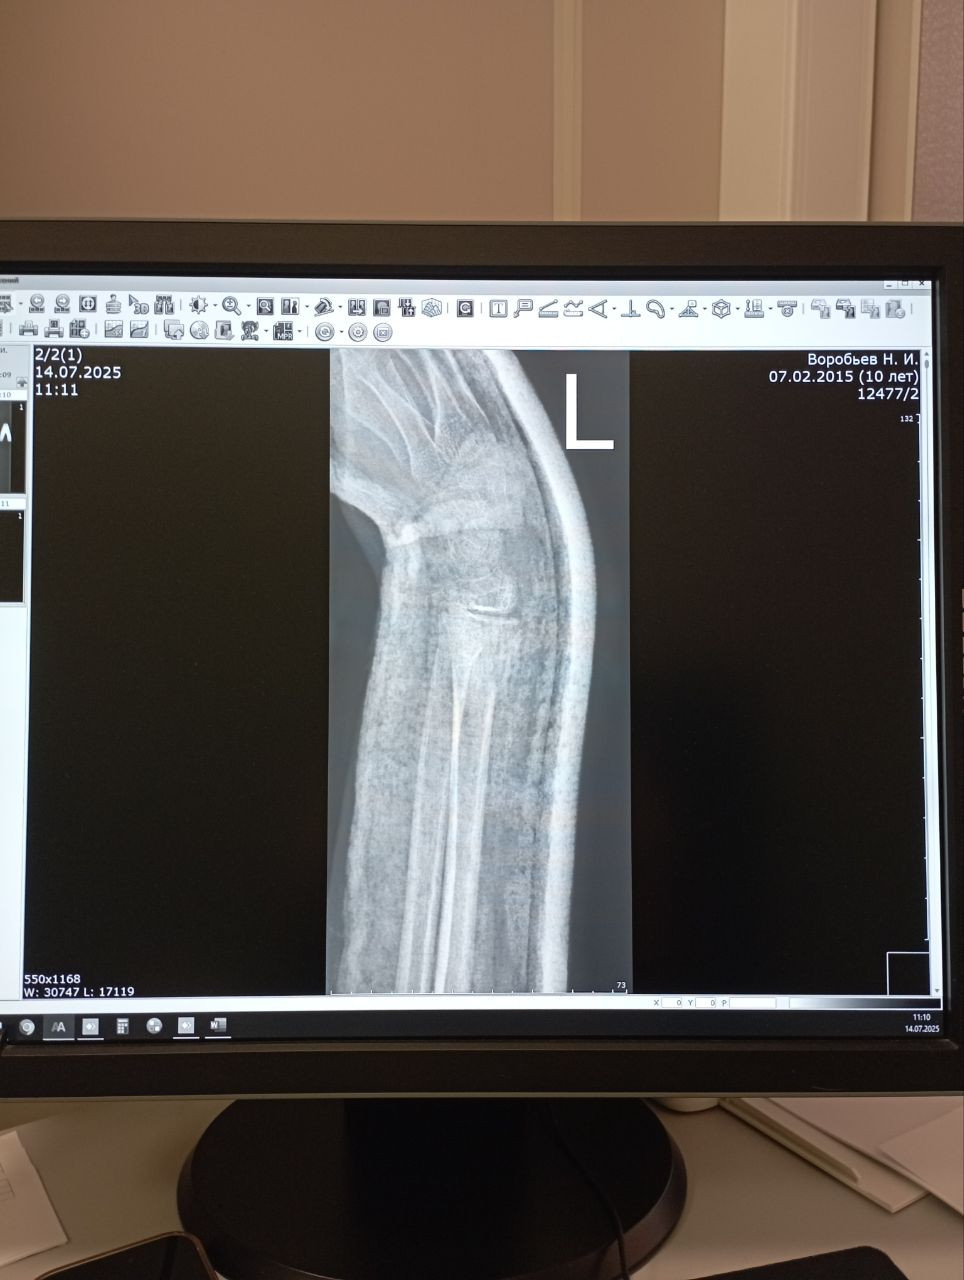

Здравствуйте. По рентгеновским снимкам видно, что перелом в области дистального метафиза лучевой кости с выраженным смещением начал формировать костную мозоль, однако линия перелома еще частично просматривается. Процесс сращения идёт, но до полноценной консолидации требуется время. Снимать гипс на 28-й день пока рано без очной оценки хирурга или травматолога. Обычно такие переломы фиксируют на 4-6 недель, в зависимости от возраста, общего состояния и стабильности отломков. Рекомендую: